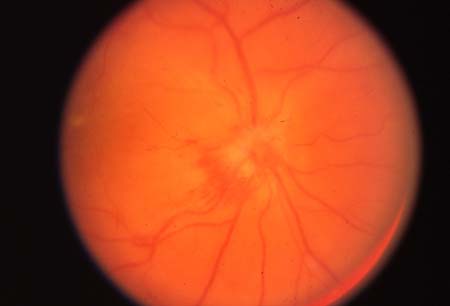

Papilite na neurite óptica

Do acervo pessoal de Dra. Cris S. Constantinescu e Dr. Thomas M. Bosley